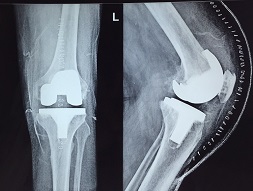

Total Knee Replacement

Tkr 69 Year Old

Tkr 73 Year Old